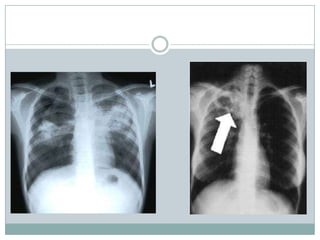

Pulmonary TB on CXR

 Primary TB- infiltrate usually in middle or lower lobe

 Ipsilateral hilar adenopathy

 Any lobe can be affected

 25% multilobar

 Endogenous TB- develops from LTBI

 Infiltrate in upper lobes

 Cavitation and collapse

 Both can have atelectasis, pleural effusions,

pericardial effusion, or lymphadenopathy

Pulmonary TB onCXR  Primary TB- infiltrate usually in middle or lower lobe  Ipsilateral hilar adenopathy  Any lobe can be affected  25% multilobar  Endogenous TB- develops from LTBI  Infiltrate in upper lobes  Cavitation and collapse  Both can have atelectasis, pleural effusions, pericardial effusion, or lymphadenopathy